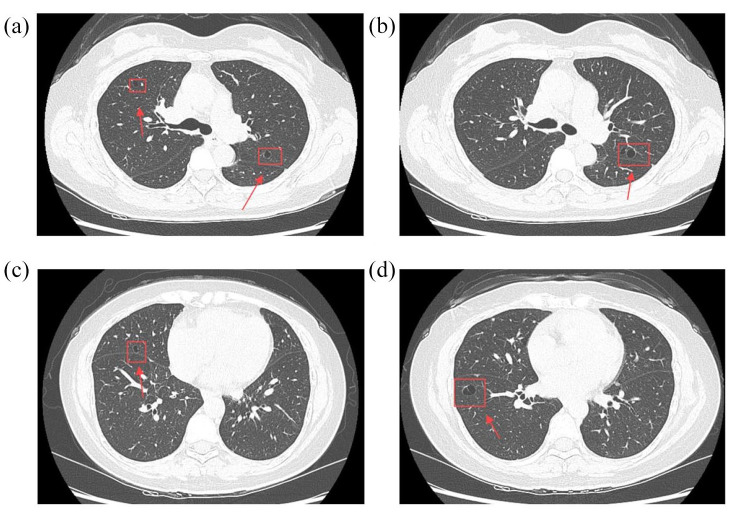

We report a case of tracheobronchial amyloidosis (TBA) in a 55-year-old woman with newly diagnosed primary Sjögren's syndrome (SS), presenting with persistent cough, hemoptysis, and dry mucosal symptoms. Chest CT showed thickened airway walls and cystic lung changes, while bronchoscopy revealed nodular lesions with exposed vessels. Congo red staining confirmed amyloid deposition with κ light-chain dominance, consistent with AL amyloidosis. Despite immunosuppressive therapy, airway lesions persisted, highlighting the challenge of managing localized amyloidosis in SS. This case underscores the need for early recognition of TBA in SS patients presenting with respiratory symptoms.